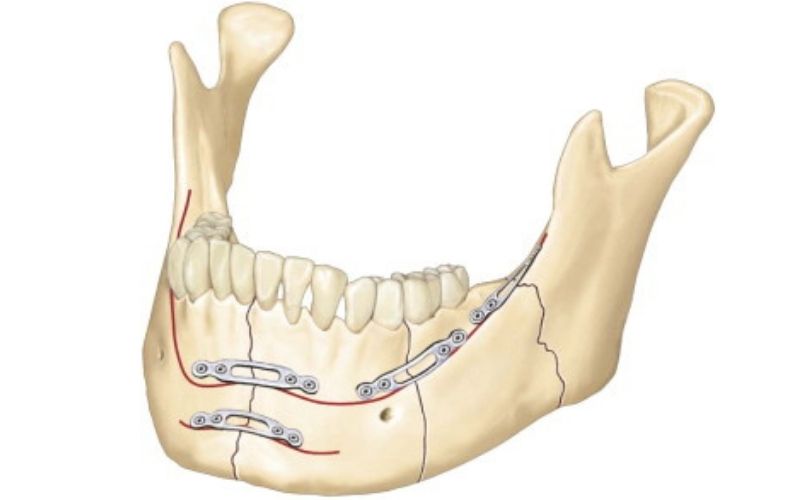

Çene Kırıkları

Travma veya zayıflamış kemikle oluşur; tedavi, kırık bölgeyi plak, vida veya tellerle sabitleyerek oklüzyonu sağlamaktır.